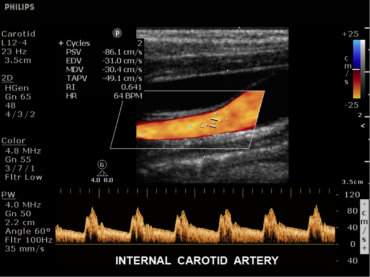

ecografo PHILIPS Clearvue 550

Progettato pensando alle esigenze di chi lo utilizza. Il sistema ecografico ClearVue 350 con tecnologia Active Array, che integra nel trasduttore le tecnologie fondamentali, garantisce una qualità eccellente delle immagini in uno strumento efficiente , affidabile ed estremamente compatto.

E’ facile perfezionare le prestazioni delle modalità bidimensionale e doppler con un solo clic, grazie all’ottimizzazione intelligente iScan che automaticamente regola e ottimizza gran parte dei parametri di uso frequente.